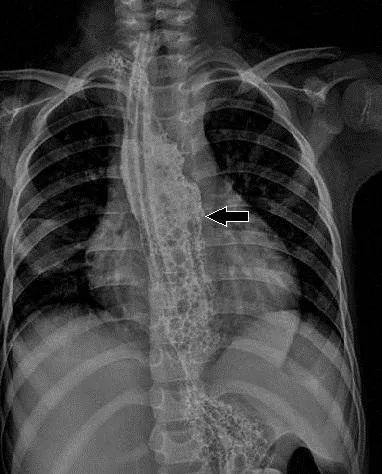

近日 , 小丽一家人找到了广东省妇幼保健院胸外科主任洪淳团队治疗 , 经过检查发现 , 小丽因误食了空调清洁剂后 , 造成了食管化学腐蚀后的狭窄 , 医生先给她尝试了无创的球囊扩张术 , 但因腐蚀后狭窄的时间较长 , 错过了保守治疗的最佳时机 , 球囊扩张并没有取得预期的效果 , 那么就只能考虑手术治疗了 。 术前的消化道造影显示:小丽食管中下段2/3严重狭窄 , 已经基本无法使用了!

文章插图

术前造影食管狭窄 通讯员供图